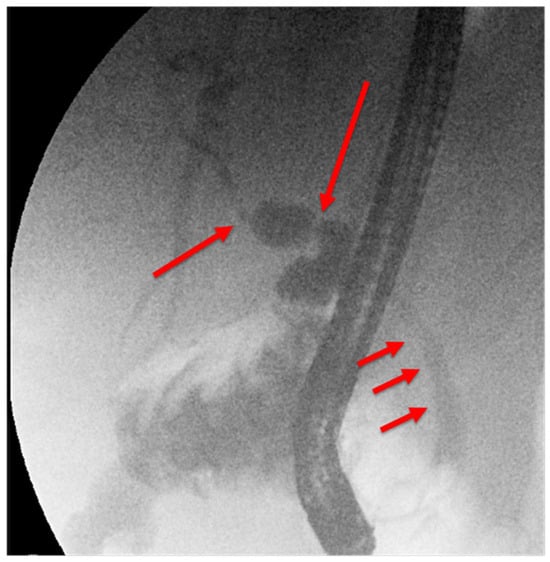

25.02: A third ERCP was performed. Fluoroscopy showed a chain of short, irregular strictures proximally (Figure 5). Digital cholangioscopy visualized irregular, friable mucosa at the hilum (Figure 6). Multiple biopsies were obtained, and a new stent was placed.

Figure 5. Third ERCP (25.02.2025): chain of short, irregular hilar strictures, suspected infiltration. (with long red arrows—pronounced alternation of dilated duct and stenosi, short arrows—subtle irregularities of the choledocus wall).